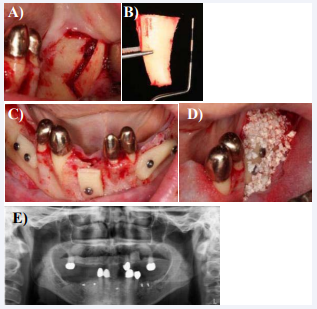

Five month after the augmentation an implant drilling template originating from the set-up was produced (Figure. 7a and Figure 7b), checked intra-orally in habitual occlusion (Figure 7c) and used to re-calculate the length of the implants to be placed with an X-ray (Figure 7d). Afterwards the implants in the upper and lower jaw were placed sub-crestally using a full thickness flap (Figure 7 e-i).

Figure 7: Preparation prior to the implant placement we fabricated implant drilling templates here in the view basally containing steel balls with a known diameter (a) in the upper jaw, (b) the lower jaw, (c) checked in occlusion and (d) with a X-ray to re-calculate the implant length and diameter. (e) Showing the upper jaw at re-entry, exposing the newly grown bone into where the implants were then placed using (f) osteotomy techniques and (g) the drilling template. (h) and (i) show the sutured situation in the upper- and lower jaw. The lower jaw implants were placed analogue to the upper jaw. (j) An OPT was taken to check the implant placement.

In order not to waste any bone we used 7osteotomy techniques in the upper jaw (Figure 7f). After suturing the wound (Figure 7h and Figure 7i), taking an OPT (Figure 7j) and removal of the stitches 14 days later, the implant were left to osseointegrate for four month. After four month the soft tissues around the implants presented themselves without any signs of inflammation (Figure 8a and b).